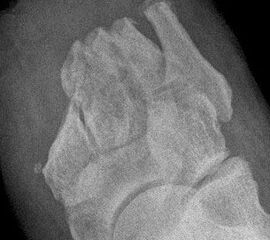

Wegen des Risikos einer Ulzeration am Metatarsalekopf (Abb. 14) sollte die Exartikulation im Grundgelenk vermieden werden. Günstiger ist es, falls möglich, einen kurzen Grundglied­stumpf als Platzhalter zu belassen (Abb. 15). Wenn Zehen in eine Lücke zu kippen drohen, kann die mit einem Platzhalter verhindert werden (Abb. 16, 17)

Es ist ungünstig, wenn wenige Kleinzehen lateral belassen werden. Das führt zum Kippen der Nachbarzehen oder zur Fehlstellung der verbliebenen Zehen (Abb. 18 - 20) und schließt eine optimale schuhtechnische Versorgung aus. Weitere Druckulzera sind zu erwarten. Die Großzehe kann als einzige Zehe belassen werden, wobei dann bisweilen die Arthrodese im Großzehengrundgelenk zur Stabilisierung ratsam ist (Abb. 21, 22).